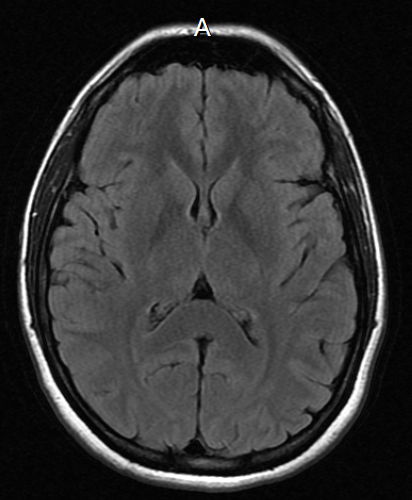

I decided to comply and go in for the MRI. I confess to being slightly non-plussed that they saw me within a week. I prefer to think of this as a little thing. A mild inconvenience. I went into the same MRI tube – not two blocks from my house – that diagnosed my left knee as appallingly damaged instead of sprained. Knowing they were taking pictures of my brain in that dark tube, I walked last summer’s Wonderland Trail trip in my mind’s eye as the beeps and tones of the MRI watched my brain light up.